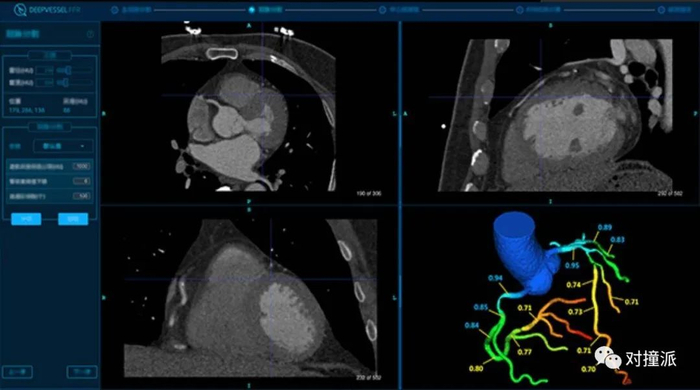

科亚的冠脉血流储备分数计数软件便是关注在这一应用点。

在目前临床上,血流储备分数(FFR)日益成为重要的量化指标,用来判断冠脉供血情况。2019年发布的《中国冠状动脉血流储备分数测定技术临床路径专家共识》中提到,“FFR已经成为评判冠状动脉缺血的金标准”。

传统的临床检查中,如果需要获得FFR,需要进行微创的介入式检查。

近年来的影像功能学出现的科研热点,则是通过CT手段,运用模拟计算获得FFR,即CT-FFR。关于CT-FFR的临床有效性,近十年来,国外已经进行过多项大型多中心实验。

科亚医疗在2016和2018年分别进行了多中心的实对比实验,将CT-FFR与介入检查得到的FFR结果进行对比。敏感性分别为94.2%,94.7%,特异性分别为84.3%,88.6%。

科亚冠脉血流储备分数计数软件界面